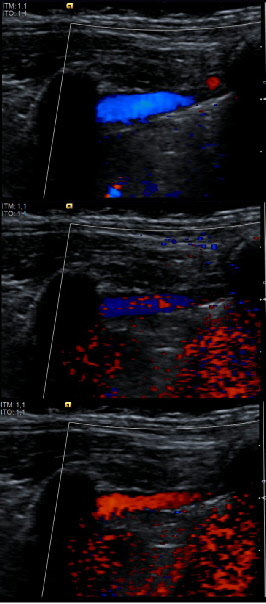

Enregistrement en mode Doppler couleur d’un épanchement pleural minime. Images consécutives d’un enregistrement au cours de la cinétique diaphragmatique révélant le flux liquidien intrapkeural

Si la valeur prédictive positive de l’échographie en échelle de gris est très élevée dans le diagnostic des épanchements pleuraux minimes, le mode doppler couleur, au pris d’une baisse notable de cette sensibilité, permet quant à lui d’accroître la spécificité diagnostique de ces épanchements [1] : le flux liquidien intra-pleural induit par la cinétique respiratoire est habituellement détectable en doppler couleur.